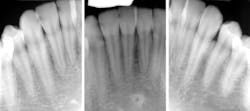

Sydney came in like clockwork every six months for recall. And at every recall appointment, she left with a treatment plan for restorative dentistry. I would start with the upper-right quadrant and work my way through over several weeks after each recall visit. After a couple of years of this, the cycle of rerestoration came full circle, and it was time for me to begin rerestoring teeth that I had worked on before. It was the same story for each restoration: recurrent decay interproximally at the gingival margin and a high plaque index, especially around the resins. At first, I took this poorly. I thought I must have sloppily placed those restorations before. I restored them again—this time bigger—with a rubber dam and moved on.

When Sydney started getting recurrent decay in the same areas around restorations that I had placed with a rubber dam, I began to understand that Sydney was different. I had already known she was different, but I had underestimated just how different she really was. She had the highest caries risk I have ever seen in my career. Three years ago, she moved to Washington, DC, for school. Her parents moved to the East Coast as well, so Sydney has become someone else’s problem.